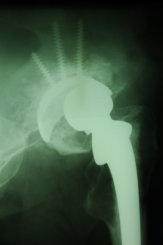

Auch heute kann trotz moderner Untersuchungs- verfahren wie z.B. Ultraschall, CT oder Kernspin- tomografie häufig auf eine normale Röntgenauf- nahme nicht verzichtet werden.

Die digital gespeicherten Röntgenbilder können schon kurz nach der Aufnahme an jedem PC-Arbeitsplatz in der Praxis betrachtet werden.

Gerne können wir Ihnen die digital archivierten Aufnahmen als Papierausdruck oder auf CD mitgeben.